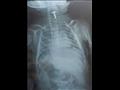

نجح فريق طبي في مستشفى الأطفال الجامعي بالمنصورة في استخراج مسمار غليظ من مرئ رضيع يبلغ من العمر ثلاثة أشهر.

بإجراء الفحوصات اللازمة والأشعة، تبين وجود جسم صلب مدبب في مرئ الطفل، فجرى تشكيل فريق طبي تحت إشراف الدكتور طارق بركات، بوحدة الجهاز الهضمي، وخضع الطفل لعملية إزالة لمسمار وجد بالمرئ.